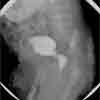

A voiding cystourethrogram (VCUG) was done: results are shown here.

The VCUG clearly shows posterior urethral valves (PUVs). The child had an impressive post-obstructive diuresis after a catheter was placed to bypass the obstruction. Several days later the urology team performed a cystoscopy and transurethral resection of the type I valves (at the 5, 7, and 12 o'clock positions). A catheter was left in place for 10 days, at which point the blood pressure, glomerular filtration rate, and levels of blood urea nitrogen and creatinine all normalized. The child is currently gaining weight and doing well.

PUVs usually appear at the earliest stage of urinary tract development. Consequently, the entire urinary tract develops in an abnormal environment of high intraluminal pressure from mechanical obstruction.3 Although 3 types of valves have been described, type I valves are found 95% of the time. This bicuspid valve radiates distally from the posterior edge of the midline prominence in the mid-prostatic urethra to the anterior proximal membranous urethra; the aperture varies to allow urine flow during voiding.3 The fused portion fills with urine and bulges into the membranous urethra, which gives the characteristic "sail-in-the-wind" finding commonly seen on VCUG (see Figure).4